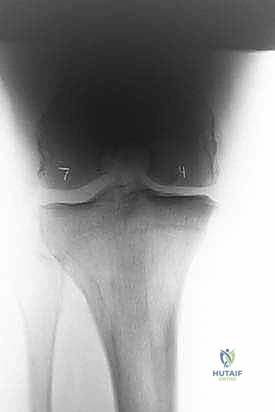

لفهم أهمية عملية (HTO)، يجب أولاً فهم كيف تعمل الركبة. مفصل الركبة يتحمل وزن الجسم بالكامل تقريباً أثناء المشي والوقوف. ينقسم المفصل إلى ثلاث حجرات رئيسية: الحجرة الداخلية (الإنسية)، الحجرة الخارجية (الوحشية)، وحجرة الرضفة (الصابونة).

في الحالة الطبيعية الميكانيكية، يمر "محور تحمل الوزن" (Weight-bearing axis) مباشرة عبر منتصف الركبة، مما يوزع الضغط بالتساوي. ولكن، عند حدوث تقوس في الساقين (Varus Deformity)، ينزاح هذا المحور إلى الداخل، مما يضع ضغطاً هائلاً ومدمراً على الغضروف الداخلي للركبة.

هذا الضغط المستمر يؤدي إلى تآكل الغضروف بشكل أسرع من الطبيعي، مما يسبب احتكاك العظم بالعظم، وهو ما يُعرف بخشونة الركبة. هنا يأتي دور الجراحة لإعادة توجيه هذا المحور نحو الجزء الخارجي السليم من الركبة.

- خشونة الركبة الأحادية (Unicompartmental Osteoarthritis): تآكل الغضروف في جهة واحدة فقط (غالباً الداخلية).

عند ظهور هذه الأعراض، يتم إجراء فحص سريري دقيق لتقييم مدى تضرر المفصل وزوايا التقوس.

تُعد الأشعة السينية (X-rays) الممتدة من الحوض إلى الكاحل (Scanogram) ضرورية جداً لحساب زاوية التقوس بدقة وتحديد مقدار التعديل المطلوب جراحياً.